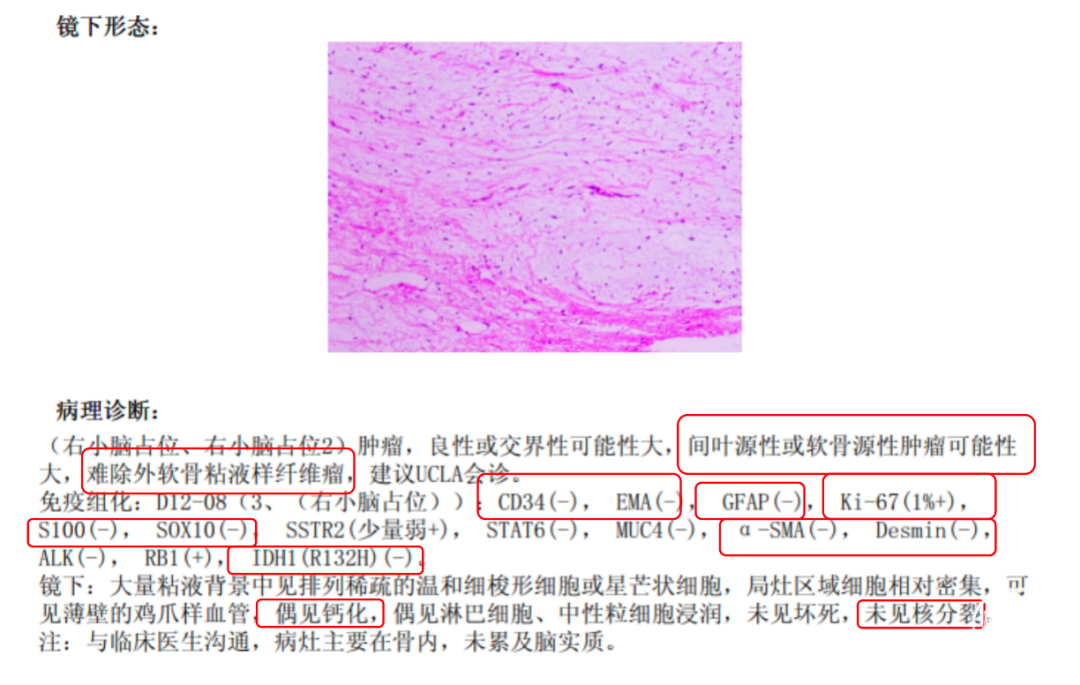

病理结果

术后常规病理提示:肿瘤,良性或交界性可能性大,间叶源性或软骨源性肿瘤可能性大,难除外软骨粘液样纤维瘤(图4)。

图4. 术后常规病理结果。

病理科讨论意见:结合该年轻患者的临床表现、影像特征及常规病理结果,得出如下鉴别诊断(图7):

1. 软骨粘液样纤维瘤(Chondromyxoid fibroma,CMF):青少年好发的良性骨内肿瘤,以黏液背景、鸡爪样血管及FOS/FOSB基因重排为特征。

2. 间叶源性肿瘤:源自间叶组织的异质性肿瘤群,涵盖良性至高度恶性亚型,免疫表型及分子变异多样(如平滑肌肉瘤、脂肪肉瘤等)。

3. 软骨源性肿瘤:以软骨分化为特征的肿瘤,如S100阳性的软骨母细胞瘤(青少年骨骺)或异型性明显的软骨肉瘤(中老年,IDH基因突变)。

本例患者为18岁女性,以头晕为主要症状,结合其年龄特征(10-30岁为颅内CMF高发年龄段)及影像学表现(边界清晰的溶骨性病变伴斑点状钙化),需优先考虑软骨源性或间叶源性肿瘤。病理学分析显示肿瘤呈分叶状结构,含丰富粘液样基质及温和的梭形细胞,核分裂象罕见,Ki-67增殖指数低(1%+),提示肿瘤恶性程度低。免疫组化结果中S-100阴性、缺乏典型组织学特征(格子样钙化、核沟、破骨巨细胞)及部位不典型排除了软骨母细胞瘤。同时,异型性缺乏及上皮膜抗原(Epithelial membrane antigen,EMA)阴性进一步排除了软骨肉瘤和间叶源性恶性肿瘤(如粘液纤维肉瘤)。尽管未检测FOS/FOSB基因重排,但结合“鸡爪样”血管模式及低侵袭性生物学行为,最终诊断为CMF。

病理学诊断

软骨黏液样纤维瘤的典型组织学表现为黏液样基质区、纤维区及软骨分化区共同构成的假小叶结构,其内可见星形或梭形细胞分布于黏液样或软骨样间质中[10]。肿瘤细胞表达Sox9及II型胶原蛋白等软骨分化标志物,小叶边缘常散在分布多核巨细胞。需注意的是,体积较大的CMF因局部细胞异型性及浸润性生长模式,需结合影像学及分子标志物与软骨肉瘤进行鉴别。